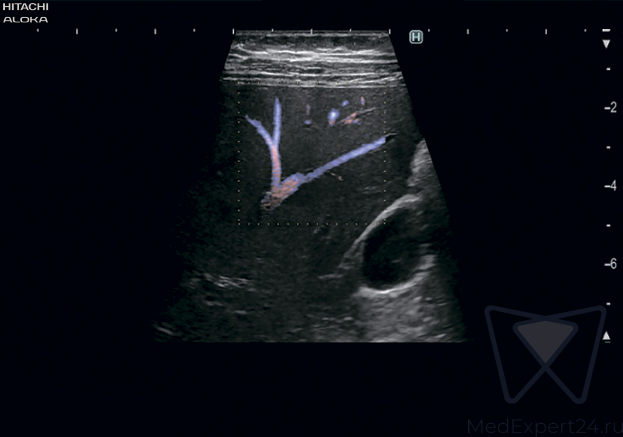

Hitachi-Aloka Lisendo 880 система УЗИ для проведения сложный кардиоваскулярных исследований. В системе доступна 2D/4D визуализация, есть аналитика и современные функции. Это новейшая система для диагностики в клинических условиях.

- Vector Flow Mapping (VFM) векторное картирование кровотока. Новая технология для исследования гемодинамики. Основной областью применения векторного картирования кровотока является исследование турбулентных потоков в камерах сердца,